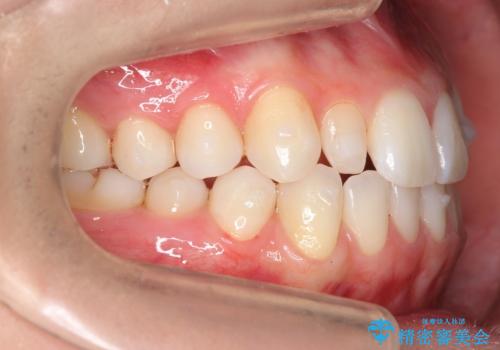

- 前歯のがたつきと小さな歯の形を治したいと来院。

前から2番目の歯が小さく、細くとがった形になっていました。

大きくしようにも、幅が少ない上に、また、内側に入ってしまっているため、矯正治療で前歯を並べてからセラミックでかぶせることにしました。

先に矯正治療をすることで、下の前歯を内側に入れることができ、上の歯のセラミックの幅や厚みを取ることができました。